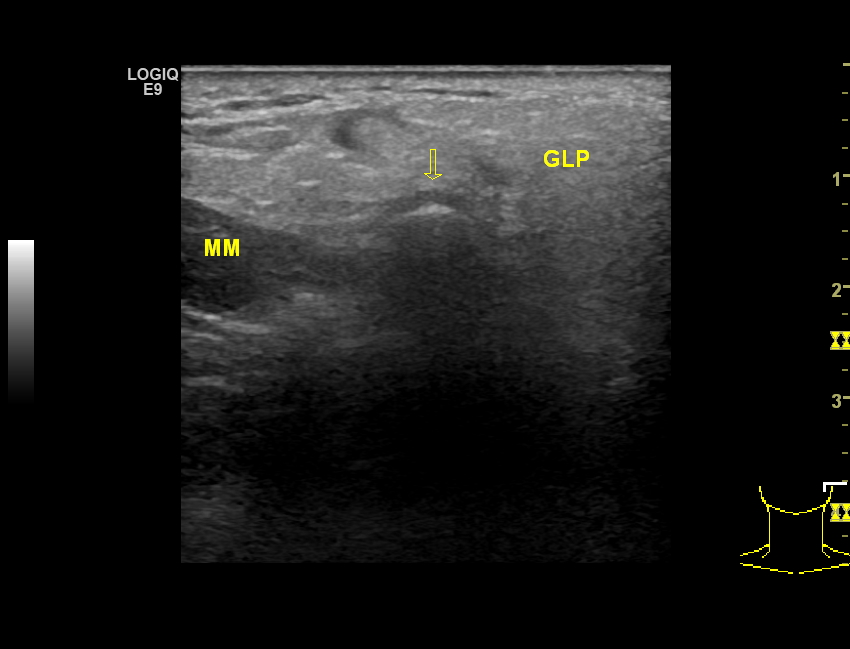

Student Image Challenge 62August 4, 2020Student Image Challenge 64August 18, 2020 Student Image Challenge 63 Student Image Challenge #63 1 / 1 Student Image Challenge #63 A 60 yo female with pain during chewing and intermittent locking of the temporomandibular joint has the following ultrasound image. What is your diagnosis? Mandible fracture Temporomandibular joint osteoarthritis Mandible dislocation Crystal arthropaty Septic arthritis Incorrect ....Please see the correct answer highlighted Correct: Temporomandibular joint osteoarthritis Your score isThe average score is 0% LinkedIn Facebook VKontakte 0% Restart quiz Case courtesy of PD Dr. med. Julian Künzel EFSUMBAdmin Related postsStudent Image Challenge 112Read more Comments are closed.